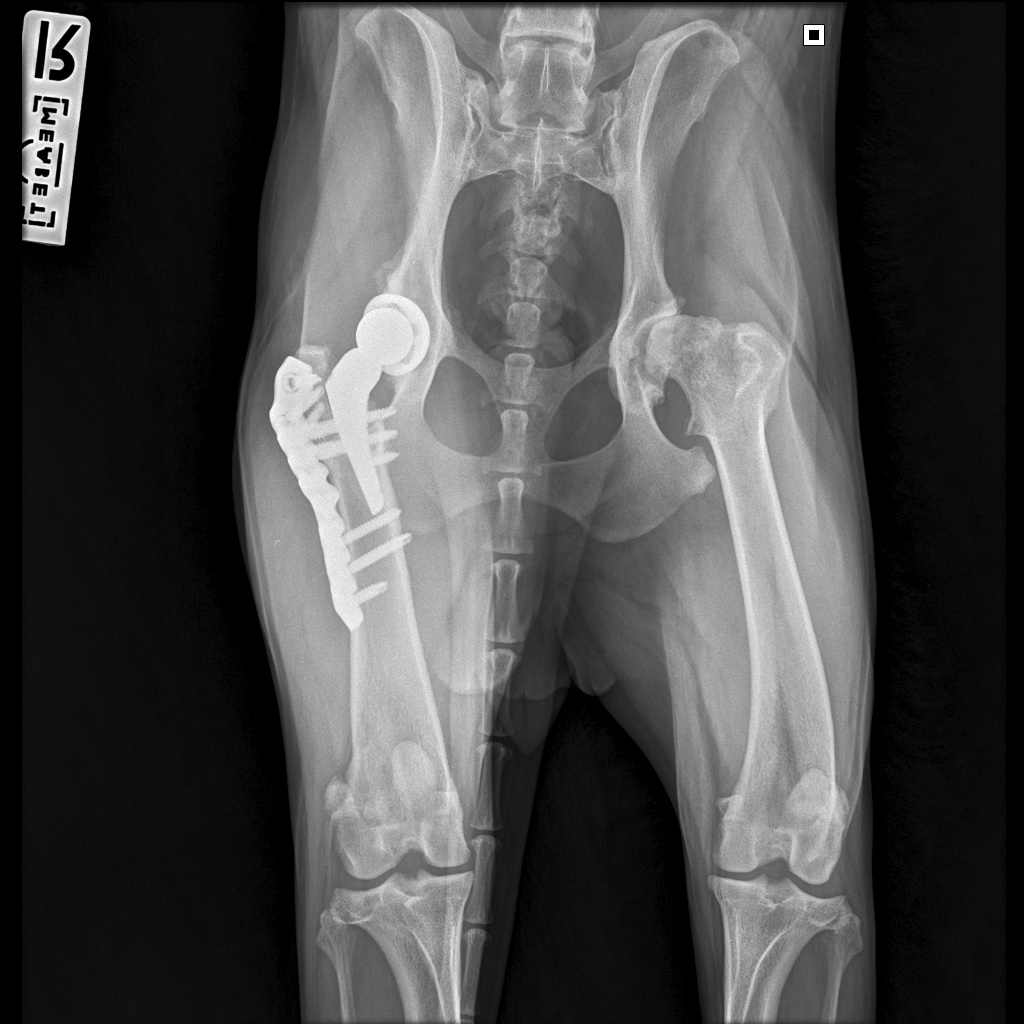

Вот как теперь выглядит ее внутренний мир

Вчера - 18.08.2025 - мы съездили на контрольный рентген. Можно было сделать рентген и в любой ближайшей клинике, но мы предпочли не рисковать. Во-первых, делать снимки нужно было в каких-то особенных проекциях, на которых виден процесс приживления, а, во-вторых, для такого рентгена требовался наркоз. Потому мы решили не искать легких путей и сразу сделать там, где гарантированно все получится в лучшем виде. Так что записались мы в Медвет в Троицке и покатили к 9 утра.

Далее стандартная процедура: разговор с доктором о самочувствии собаки и наличии жалоб, осмотр анестезиологом и Басю забрали. Где-то через час нам вернули ее уже полностью отошедшую от наркоза, сказали, что все у нас хорошо, ограничения с нас сняты и мы можем быть свободны.